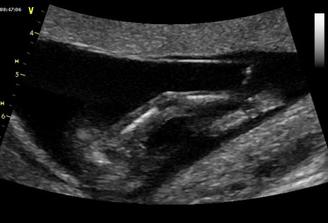

14.7.2009 jsme byli s taťkou na velkém UTZ (22+3) u pana MUDr. Břešťáka. Pan doktor byl fajn, ukázal nám miminka srdíčko, frekvenci srdíčka, tok krve do srdíčka a do aorty, játra, ledviny, močový měchýř..., dokonce i základy zoubků. Změřil všechny orgány a tělíčko a byl moc spokojený, vše je tak, jak má být. Nakonec nám potvrdil, že čekáme HOLČIČKU! Mrskala s sebou , chvíli trvalo, než pan doktor mohl změřit srdeční frekvenci. Vážíme 492g. Jsme s tatínkem moc šťastní, že je malá v pořádku. Dneska objednáme kočárek casualplay s4. Tak dneska 26.7.2009 jsme se byli s tatínkem podívat na naši holčičku na 4D UTZ. Udělali nám dvd a fotečku. Malá se nejdřív moc nechtěla ukazovat, schovávala se a točila se k nám zády. Pak si ale dala říct a krásně se nám ukázala. Je moc hezká, je to celý tatínek. Má jeho nosánek, pusinku, bradičku. Byla to sranda, zívla si a dala si nožičku k pusince, pak se pošťourala v oušku. A je to malá čertice, mrskala s sebou pěkně. Když jsme si jí doma prohlíželi na dvd, tak taťkovi dala pořádný kopanec, až vyskočil. 4D UTZ je fajn a my jsme spokojení. 4.8.2009 jsem byla na testu na cukrovce, ble. Ale nebylo to tak hrozný a máme splněno. 5.8.2009 jsme volali na vysledky jak nám cukrovka dopadla a výsledky jsou v pořádku, jupíí. Hnedka jsem to oslavila 2x koblihou a 2x croisantem. 11.8.2009 jsme byli na kontrole, malinká je v pořádku a je otočená hlavičkou dolů. Paní doktorka říkala, že je šikovná a že si myslí, že už takhle zůstane. Tak konečně uběhl měsíc a kousek a my se jdeme s taťkou podívat na naši holčičku. Paní doktorka říkala, že bude Michalku měřit, jsme totiž 32. týden. Paní doktorka malou změřila, odpovídáme úplně na den 31+3 a vážíme 1445g. Paní doktorka říkala, že Michalka je krásně proporční miminko, úplně podle tabulek a že by měla při porodu mít okolo 3500g. Michalka je moc šikovná, je stále hlavičkou dolů. Jupííí, jsme s tatínkem moc rádi. 01.10.2009 jsme byli u paní doktorky na další kontrole a Michalka se má dobře, krásně jí tlouklo srdíčko a je stále hlavičkou dolů, jupíí. Dostali jsme formulář na mateřskou a od 09.10.2009 na ní nastupujeme, jůůů, toto letí. Tak dneska je 13.10.2009 a byli jsme na poslední kontrole u naší paní doktorky, malá se má dobře, hlavičkou je stále dolů a váží 2300g, je to pěkný cvalík. Máme s tatínkem radost. CS máme 2. Už budeme chodit na kontroly do porodnici v Motole, kam se musíme objednat. 27.10.2009 jsem byla poprvé v poradně v Motole, paní doktorka nás vyšetřila, CS asi 4, pak jsme poslouchaly srdíčko naší malé princezny, zrovna cvičila spartakiádu. Kontrola v pořádku. Další kontrola bude i s monitorem, tak se moc těšíme. Dnes 03.11.2009 jsem byla v poradně v Motole, poprvé nám dělali monitor a malá se tak vrtěla, až mi sklouzla sonda a musela jsem si jí tam pak držet. Malá měla výsledky monitoru v pořádku, tak jsme moc s tatínkem rádi. Paní doktorka mě dnes nevyšetřovala, až zase na příští kontrole. Dneska je 10.11.2009, náš další den, kdy jsme se vydali do poradny. Natočili nám monitor, výsledky monitoru jsou v pořádku a paní doktorka mě i vyšetřila. CS 4, čípek zkrácený, měkký, hlavičkou je hezky nastavená. Je to naše malá šikulka a už se na ní s tatínkem móóc těšíme!!!